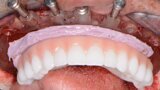

Fig. 14: PMMA maxillary and mandibular restorations.